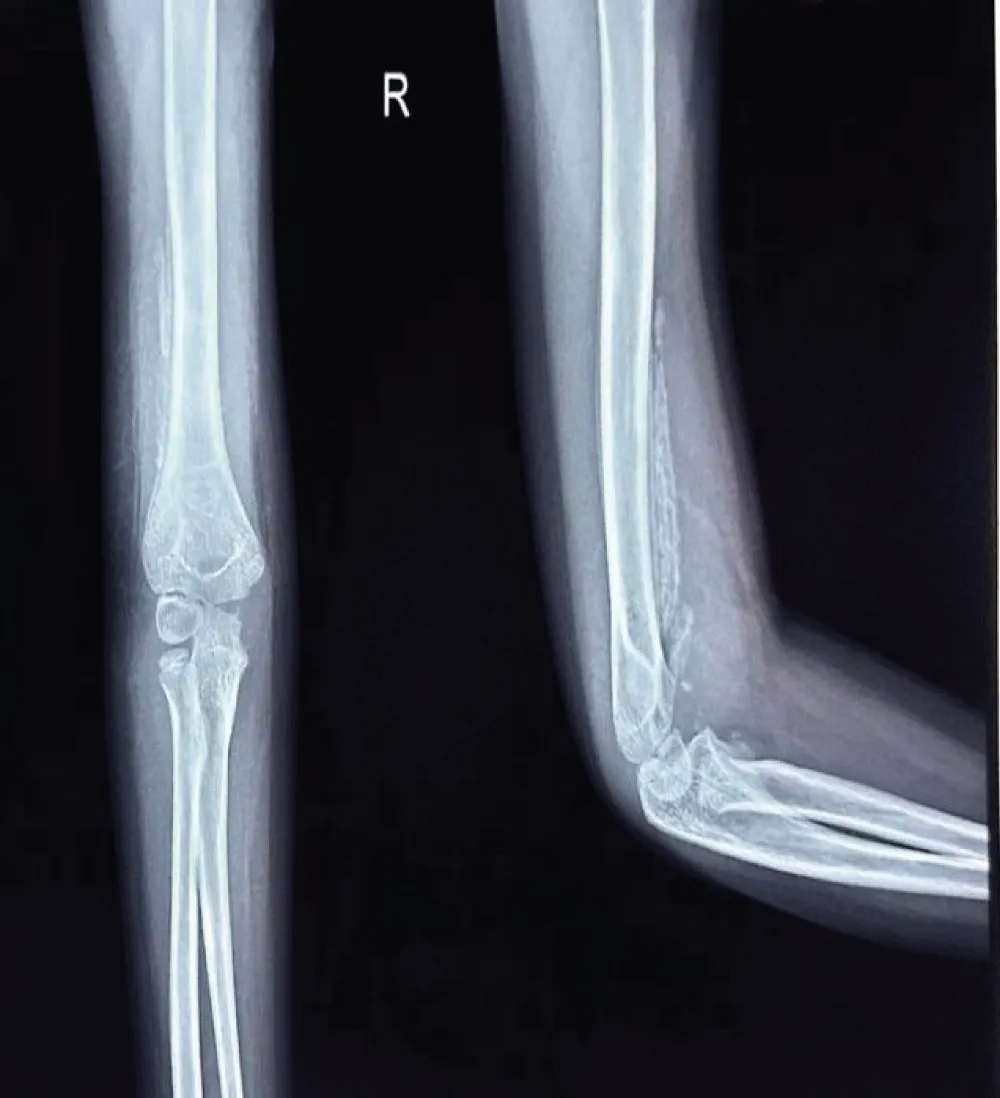

A mother with 6 year old female child presented to our Orthopedic Out Patient Department. She had not been able to move her right elbow in full range with restricted active and passive movements and appeared distressed. According to the informant (mother), she had been apparently well 2 months back when she was hit by rear wheels of a tractor while playing on the roadside. She developed pain and swelling in the elbow and was immediately rushed to the nearby hospital. Routine investigations, CT scan of abdomen and pelvis and X-ray of right elbow and hand were done. (Figures 1-3). All reports were normal except X-ray arm diagnosing undisplaced low lying supracondylar fracture of the right humerus (Figure 3). The child was admitted to the hospital and right upper limb was immobilized in an above-elbow plaster slab, with the elbow in 90o flexion (Figure 4). She was discharged after 4 days with reportedly normal radiographic findings.

However, the child continued to experience persistent pain and stiffness in the elbow region, progressively limiting the range of motion. This prompted another hospital visit, during which an X-ray of the right elbow was obtained (Figure 5). Subtle calcific changes-early signs of heterotopic ossification-were present but went unnoticed. Physiotherapy was initiated under the assumption of post-immobilization stiffness. However, within a few days of physiotherapy, the patient developed worsening stiffness and a painful, enlarging subcutaneous lump in the elbow region.

Radiograph of the elbow joint revealed a well-defined calcified mass parallel to the humerus, with a convex shape extending along the supracondylar region with the classical features of heterotopic ossification. The patient guardians declined further advanced imaging studies, including MRI, citing personal reasons. Consequently, the diagnosis of Myositis Ossificans Traumatica was made based exclusively on radiographic findings.

Radiological imaging showed residual heterotopic ossification along the humerus, indicating incomplete resolution. Multiple radiographs of the right upper limb-including the arm, forearm, and elbow joint were taken during outpatient visits at the patient’s convenience and were compared over time to monitor progress (figure 7,8). A well-visualized radiograph obtained 10 months after the initial injury showed near-complete resolution of the heterotopic ossification (Figure 9).